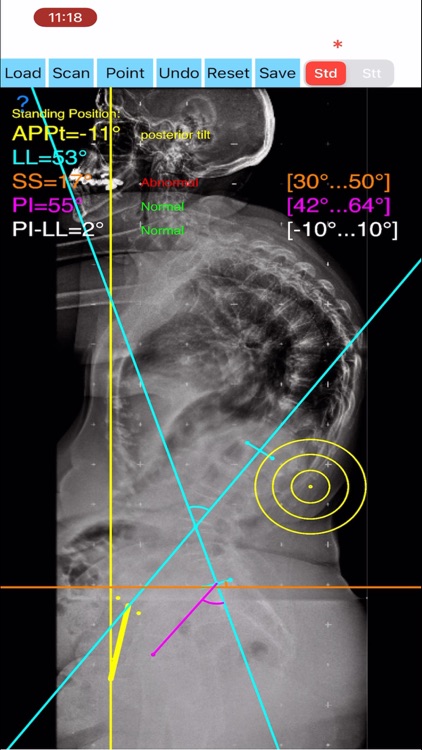

Evaluation of functional spinopelvic imaging in lateral radiographs in sitting and standing positions is of importance, especially in patient before total hip replacement surgery. Patients with concomitant hip and spine pathology undergoing primary total hip were identified as being at high risk for dislocation. Instability-prone patients arhtroplasty (THA) should appropriately assessed for the presence of deformity and abnormal spinopelvic mobility. The preoperative planning for THA should encompass evaluation of functional spinopelvic imaging in lateral radiographs in sitting and standing positions. Before planning cup position the surgeon should taken into account also anterior pelvic plane (APP) the coronal (functional) plane and the anterior pelvic plane tilt APPt or pelvic tilt and abnormal spinopelvic mechanics from standing to sitting.

The App is software aimed for orthopaedic surgeons, and allow to:

- mark certain points at the image of X-ray, and calculate at once the anterior pelvic plane tilt (APPt) or pelvic tilt , Pelvic incidence (PI), Sacral slope (SS), Lumbar lordosis (LL), Pelvic incidence Angle (PI) minus Lumbar lordosis Angle (LL)(PI–LL).

-to classify the patient into one of four Categories of the Hip-Spine Classification (1A,1B,2A,2B) by integrating spinal alignment (spinal deformity defined at PI-LL mismatch >10 degree(1)

-cases are categorised to group-specific recommendations for acetabular cup position respectively thus with minimal measurements will effectively identify the complex “hip-spine” THA patient at high risk for postoperative instability (1).

-According to measured parameters in standing and sitting lateral x- rays - based n a busy everyday practice, app offers a convenient way to perform radiographic measurements for spine, at the spinopelvic juncture - combing sitting and standing X-Rays, in a blink of an eye in front of your screen. The build in features of the app, allows results to be categorized and may help identify the complex “hip-spine” THA patient at high risk for postoperative instability and helps planning the optimum cup placement.